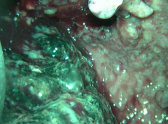

На фотографии, сделанной во время операции, виден фрагмент некротизированной поджелудочной железы чёрного цвета, который был удалён из полости абсцесса. Этот снимок – наглядное свидетельство того, от какой страшной болезни удалось избавить пациента благодаря мастерству воронежских хирургов.